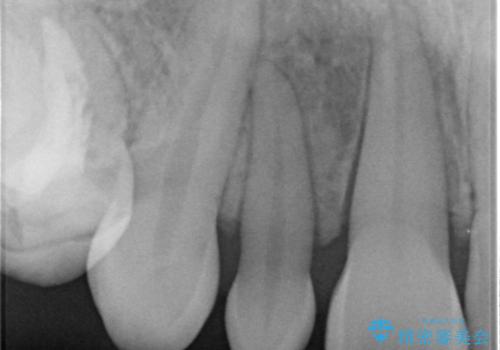

前歯の審美的なブリッジ (歯列矯正後)

- 歯列矯正後に前歯にブリッジを入れた方の経過です。

矯正治療で歯の位置を整えてからブリッジを入れると歯の幅を自由に設定できるため、左右対称にできます。結果矯正なしでいきなりセラミックにする場合と異なり、無理に角度を変えたりする必要がなく、神経をなるべく温存したまま審美的なセラミック治療が行えます。